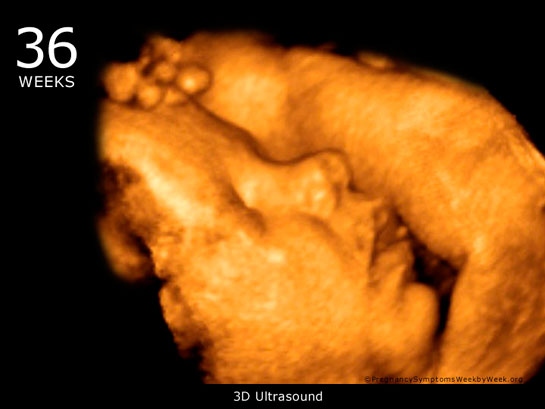

36 Haftalık Gebelik

36 haftalık gebelik, fetüsün gelişimi ve anne adayının sağlığı açısından kritik bir dönemdir. Bu süreçte, sağlıklı beslenme, düzenli doktor kontrolleri ve doğum hazırlıkları büyük önem taşır. Ayrıca, anne adaylarının ruhsal ve fiziksel sağlığına dikkat etmeleri, başarılı bir doğum deneyimi için gereklidir.

| 36 haftalık gebelik, bir hamilelik sürecinin önemli bir aşamasını temsil eder. Bu dönem, fetüsün gelişiminde kritik bir dönemdir ve anne adayının sağlığı bakımından da dikkate alınması gereken birçok faktör vardır. Bu makalede, 36 haftalık gebelik sürecinin özellikleri, anne adayı ve fetüs üzerindeki etkileri ile birlikte, bu dönemde dikkat edilmesi gereken konular ele alınacaktır. Fetüs Gelişimi 36 haftalık gebelikte fetüs, doğuma oldukça yakın bir dönemde bulunmaktadır. Bu aşamada fetüsün gelişimi ile ilgili bazı önemli noktalar şunlardır:

36 haftalık gebelik sürecinde yaşadıklarım gerçekten çok ilginç. Bebeğimin boyunun 47 cm ve ağırlığının 2 kg 700 gram olması beni heyecanlandırıyor. Her gün ortalama 30 gram alması da bu süreçteki gelişimini gösteriyor. Bebeğin doğuma hazırlandığını bilmek güzel ama bu haftayı atlatmanın verdiği rahatlıkla birlikte üzerimdeki yükün biraz hafiflemesi de sevindirici. Hormonal değişimler nedeniyle bedenimdeki gevşeme ve yumuşama beni yavaşlatıyor. Yürüyüşlerim değişti, bu da normal. Ancak bel ve pelvisteki ağrılar beni rahatsız ediyor. Yemek yeme konusunda da sıkıntılar yaşıyorum, bebeğim artık çok yer kaplıyor. Küçük porsiyonlarla beslenmek zorundayım. Mide yanmamın hafiflemesi, nefes almamı kolaylaştırdı ama bebeğim aşağı doğru inmeye çalıştıkça alt karın bölgesinde baskı hissediyorum, bu da rahatsız edici. Braxton Hicks kasılmalarının daha fazla hissedilmesi de dikkatimi çekiyor. Doğum sancılarının başlaması için her an hazırlıklı olmam gerektiğini biliyorum. Bebeğimin hareketlerinde azalma olursa ya da vajinal kanama yaşarsam hemen doktora gitmem gerektiğini unutmayacağım. Vajinal akıntıdaki artış beni endişelendiriyor ama cinsel birliktelikten sonra lekelenmenin normal olduğunu öğrenmek biraz olsun rahatlatıyor. Karın kaşıntım da dayanılmaz hale geldi; badem yağı ve E vitamini kremleri kullanmaya başladım. Uyku sorunlarıyla başa çıkmak için rahat kıyafetler giymek zorundayım. Ayaklarımda ve bileklerimdeki şişlik beni oldukça rahatsız ediyor fakat bol sıvı tüketmeye dikkat ediyorum. Halsizlik hissi normal ama doğumun yaklaşmasıyla birlikte bir enerji patlaması yaşıyorum. Artık tuvalet ihtiyacım da arttı, bu durum da yeni bir alışkanlık haline geldi. Tüm bu süreç gerçekten hem zorlu hem de heyecan verici!